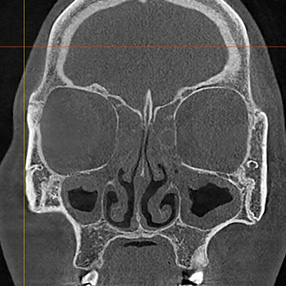

※ 축농증 수술 후 생길 수 있는 부작용으로는 출혈, 감염, 염증이 있을 수 있습니다.

본 사진은 의료기관에서 진료를 본 환자이고, 전후 사진 인물이 동일인이며,동일조건에서 촬영이 되었습니다.